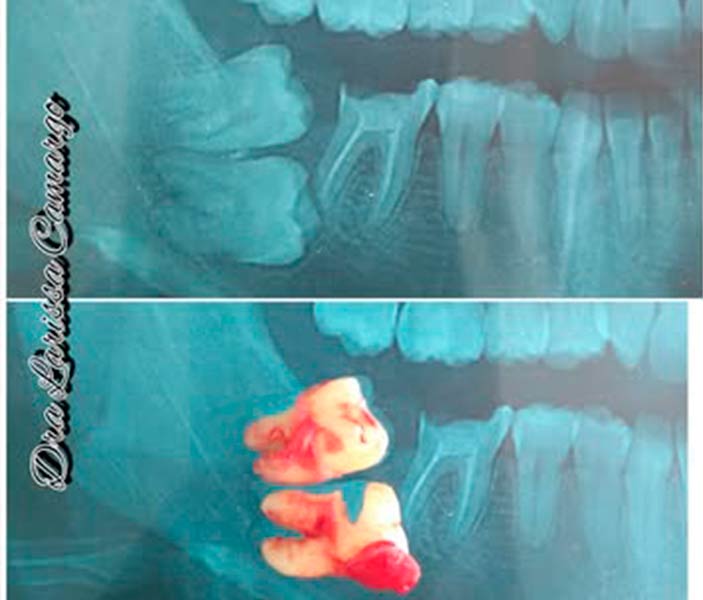

Casos reais de cirurgias de extrações

Veja alguns casos reais de cirurgias realizadas pela Dra Larissa Camargo